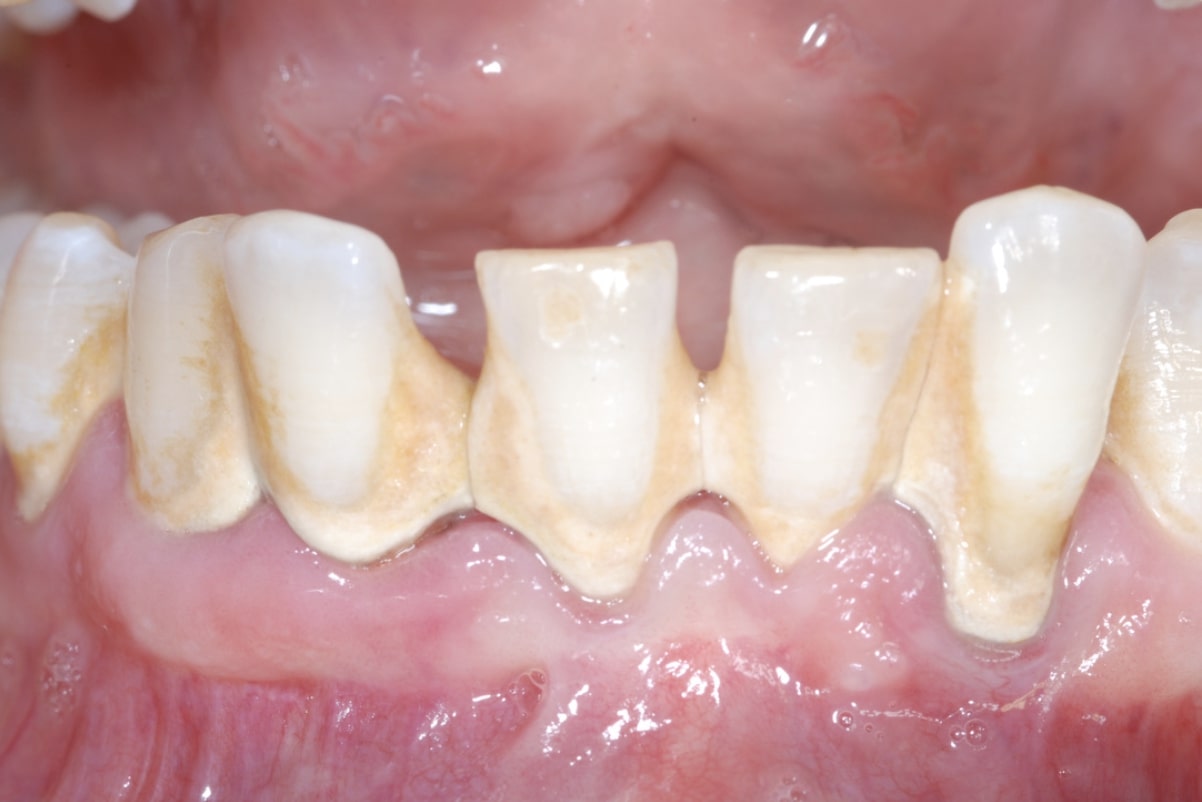

Si definisce quindi scaling quella procedura di base con la quale il tartaro viene rimosso dalla superficie dentaria. A sua volta poi si parla di scaling sopra-gengivale quando la terapia si esplica su tartaro visibile situato al di sopra della gengiva (vedi figura 1), oppure viene definito sub-gengivale quando si esplica su tartaro che è nascosto sotto la gengiva.